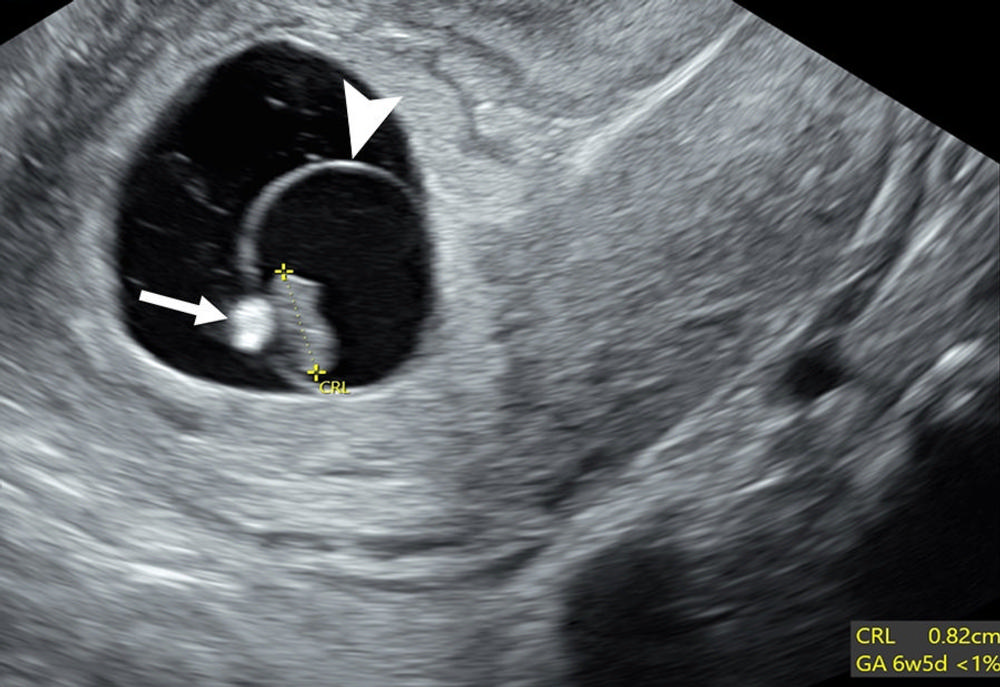

Figure 16. Poor prognosticators: calcified yolk sac and expanded amnion sign. Transvaginal sagittal grayscale US image in a 27-year-old pregnant patient shows an 8-mm embryo (calipers) without cardiac activity (M-mode not shown) sufficient for the interpretation of diagnostic of early pregnancy loss (EPL). Additional poor prognosticators include a calcified yolk sac (arrow) and an enlarged amniotic cavity (arrowhead) relative to the crown-rump length (CRL) of the embryo, called the expanded amnion sign. These additional observations, on their own, are only concerning for EPL. GA = gestational age.

High-res (TIF) version